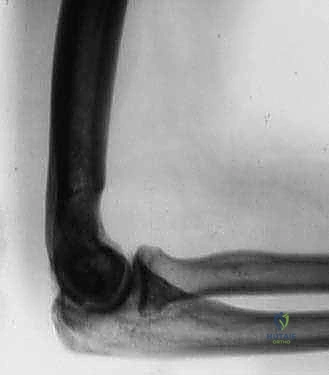

- الأشعة السينية (X-rays): الفحص الأساسي لرؤية العظام. تُظهر الأشعة السينية بوضوح تضيق المسافة المفصلية، وجود النتوءات العظمية (المهماز العظمي) في الحفرة الزجية والإكليلية، والأجسام الحرة الكبيرة.

- الأشعة المقطعية ثلاثية الأبعاد (3D CT Scan): تُعد الأداة الأهم للتخطيط الجراحي لعملية أوتبيردج-كاشيواجي. توفر خريطة دقيقة ثلاثية الأبعاد لحجم وموقع النتوءات العظمية، وتساعد الدكتور هطيف على تحديد كمية العظام التي يجب إزالتها بدقة مليمترية.

- ألم ميكانيكي: ألم يزداد مع استخدام الذراع ويقل مع الراحة. غالباً ما يكون الألم في ذروته عند محاولة فرد الكوع بالكامل (مثل محاولة الوصول لشيء بعيد) أو ثنيه بالكامل (مثل محاولة لمس الكتف أو حلاقة الذقن).

- فقدان نطاق الحركة (Stiffness): هذا هو العرض الأكثر شيوعاً. يلاحظ المريض تدريجياً أنه لا يستطيع فرد ذراعه بشكل مستقيم، أو لا يستطيع ثنيها لتناول الطعام بشكل مريح.

سُميت هذه العملية تيمناً بالجراحين اللذين قاما بتطويرها. تعتمد الفكرة الأساسية لهذه الجراحة العبقرية على مبدأ ميكانيكي بسيط ولكنه فعال للغاية. في الكوع المتيبس بسبب الخشونة، تتكون نتوءات عظمية في الجزء الأمامي (الناتئ الإكليلي والحفرة الإكليلية) والجزء الخلفي (الناتئ الزجي والحفرة الزجية).

بدلاً من إجراء شق جراحي أمامي وشق جراحي خلفي كبيرين للوصول إلى هذه النتوءات، يتم الوصول إلى المفصل من الخلف فقط. يقوم الدكتور هطيف بإزالة النتوءات العظمية الخلفية، ثم يقوم بـ إحداث ثقب (Fenestration) أو نافذة دقيقة في العظم الرقيق الفاصل بين الحفرة الزجية (الخلفية) والحفرة الإكليلية (الأمامية) لعظمة العضد.